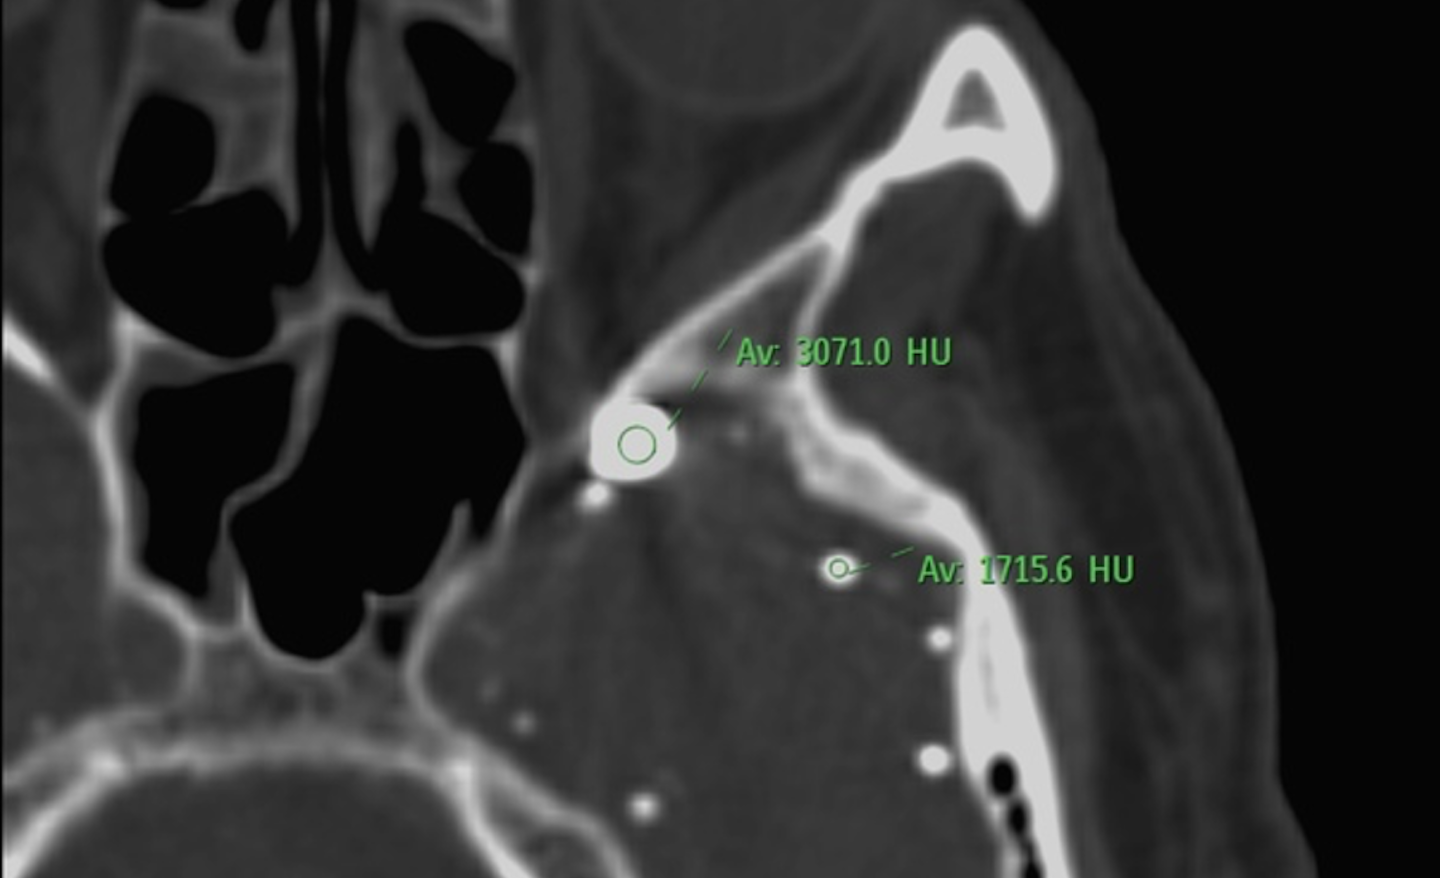

REMANENTES DE CONTRASTE INTRATECAL POR TC

CASO CLÍNICO - EVALUACIÓN POR TOMOGRAFÍA COMPUTADA INTRODUCCIÓN

• Paciente varón de 75 años con antecedentes cardiovasculares relevantes.

• Se solicita tomografía computarizada cerebral ante sospecha de nuevo evento cerebrovascular.

ANTECEDENTES MÓRBIDOS

• ACV isquémico en territorio de la arteria cerebral media (ACM) derecha hace 1 año.

• Hipertensión arterial crónica en tratamiento

• Antecedente quirúrgico de HNP intervenida hace 40 años.

...